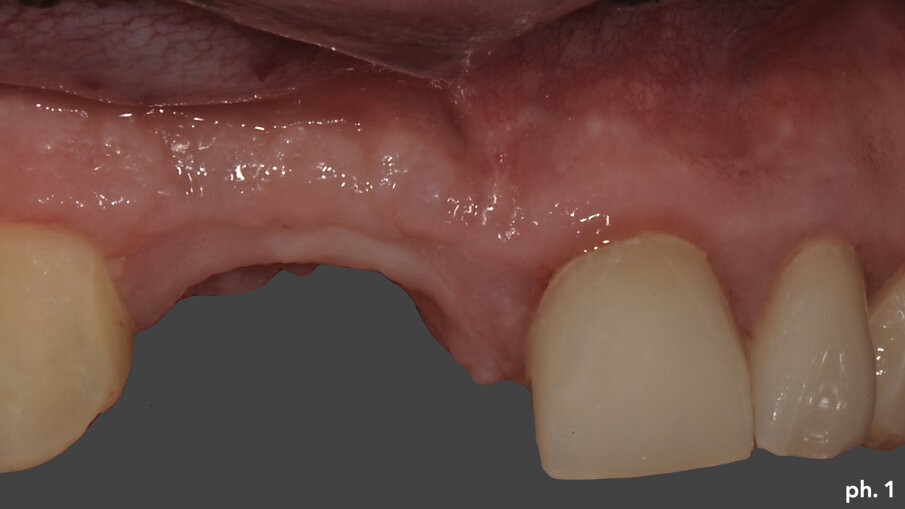

Il paziente, maschio caucasico di 28 anni, si presenta alla nostra osservazione in seguito a un incidente che ha provocato l’avulsione traumatica degli elementi 1.1 e 1.2 con conseguente riduzione dei volumi ossei della zona che, oramai, risulta parzialmente edentula. Sono inoltre presenti in corrispondenza degli elementi 2.1 e 2.2, anch’essi coinvolti nel trauma, due elementi provvisori in resina. La richiesta del paziente è quella di riabilitare la zona edentula con impianti e finalizzazione protesica da 1.2 a 2.2 con corone singole in ceramica1, 2. Dall’esame clinico si evidenzia una carenza di tessuto osseo sia in senso verticale (Fig. 1) che in senso orizzontale (Fig. 2). Si è deciso quindi che l’opzione terapeutica migliore per ottenere una buona rigenerazione ossea di tipo combinato, fosse quella di utilizzare una griglia in titanio customizzata3 in combinazione con un mix di osso bovino deproteinizzato (Geistlich Bio-Oss) e chips ossei prelevati nella zona operata tramite l’utilizzo di un un safe-scraper (Meta)4, il tutto ricoperto da uno strato di matrice Mucograft. Il protocollo operativo delle griglie in titanio customizzate Yxoss CBR prevederebbe l’utilizzo di una membrana in collagene come Geistlich Bio-Gide nella ricopertura della stessa. Personalmente in alcuni casi da me trattati ho deciso di sostituire la membrana in collagene con la matrice, sempre in collagene di origine suina ma in questo caso ricostituito, soprattutto nei settori estetici laddove è richiesta una maggiore quantità di tessuto cheratinizzato al fine di ottenere un risultato estetico migliore. Una volta esposto quindi il tessuto osseo (Figg. 3, 4), si è provveduto ad effettuare una serie di perforazioni a livello della corticale ossea al fine di favorire un regolare sanguinamento (Fig. 5): questo permetterà ai nostri materiali da rigenerazione di usufruire di una maggiore quantità di fattori di crescita, proteine morfogenetiche, ed ottenere quindi una loro migliore integrazione nel tempo.